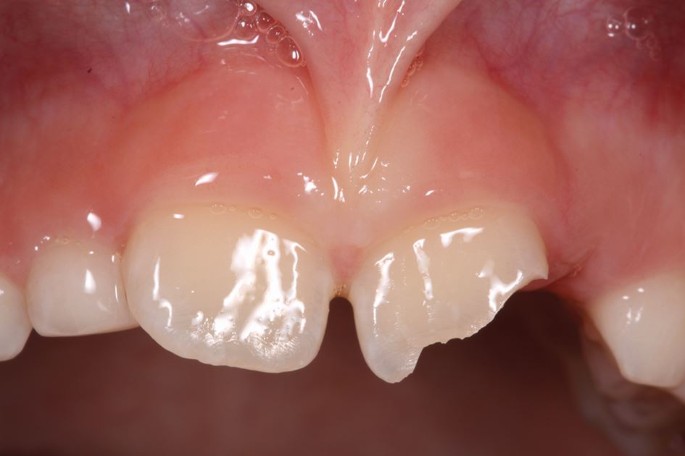

Delays in treatment may occur from athlete behaviour (late arrival, underestimating urgency, uncooperativeness) and healthcare factors (staff knowledge, accident and emergency department waits, triage). Effective care follows three phases: acute (within three hours), subacute (24 hours), and delayed (over 24 hours), as categorised by Andreasen et al.,43 to be followed alongside IADT guidelines34,35,36,37 for structured management (Table 3; Figures 10, 11, 12, 13, 14, 15, 16 and 17).

An uncomplicated enamel-dentine fracture

A complicated enamel-dentine fracture